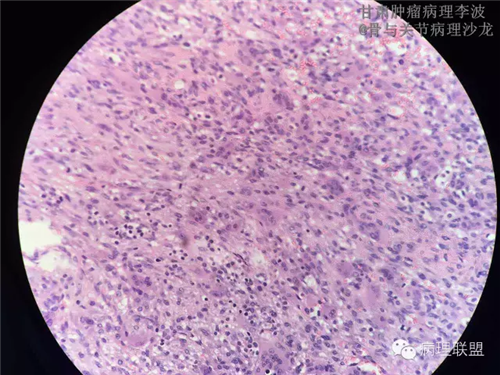

M/14 骶骨骨肉瘤-张惠箴讲解

病例由甘肃肿瘤病理 李波 提供,致谢。